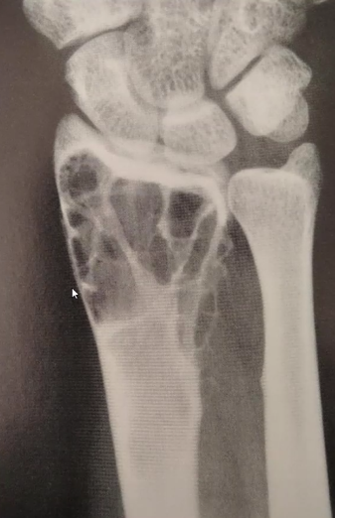

Tumeur à cell géante (ostéoclastome) : 80% bénin 20% Malin

- 20-40 ans

- Prompt à fx patho

- Touche les os longs, subarticulaire, près plateau physe, soap bubble apparence

- « Soap bubble appearance », plusieurs compartiments

- Bien défini, petite zone de transition (bénin)

- Moins bien défini et longue zone de transition (malin)

- Distal radius ++ (malin)

- Risque de tourner en ostéosarcome